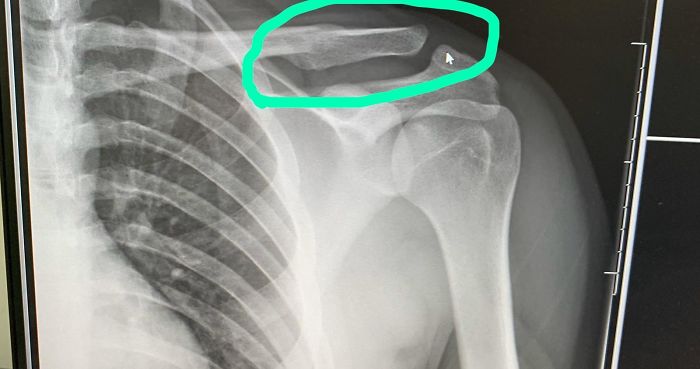

Went Through 21 Years Thinking I Never Broke A Bone Until An X-Ray For A Shoulder Problem Revealed This Atrocity, It Broke And Healed Without Me Knowing, Was Nice Knowing You

It could happened when he/she was a baby. You'd think you'd notice but if it happens at birth, it can easily be missed